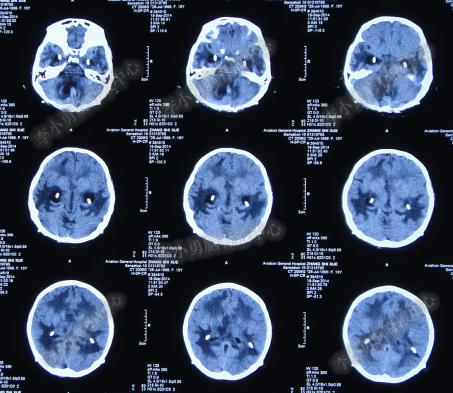

第3次手术右侧脑室外引流术后1个月时间内,脑积水仍没有得到控制,再给予腰大池引流,期间多次试图拔除右侧脑室外引流管(多次调高脑室外引流管的高度),但因患者意识变差,而无法拔除引流管,给予拔除腰大池引流,治疗期间曾多次查头部CT均示脑积水仍无改善(图-20、图-21、图-22、图-23)。

图-20:2014年7月24日头部CT

图-21:2014年7月29日头部CT

图-22:2014年8月4日头部CT

图-23:2014年8月15日头部CT